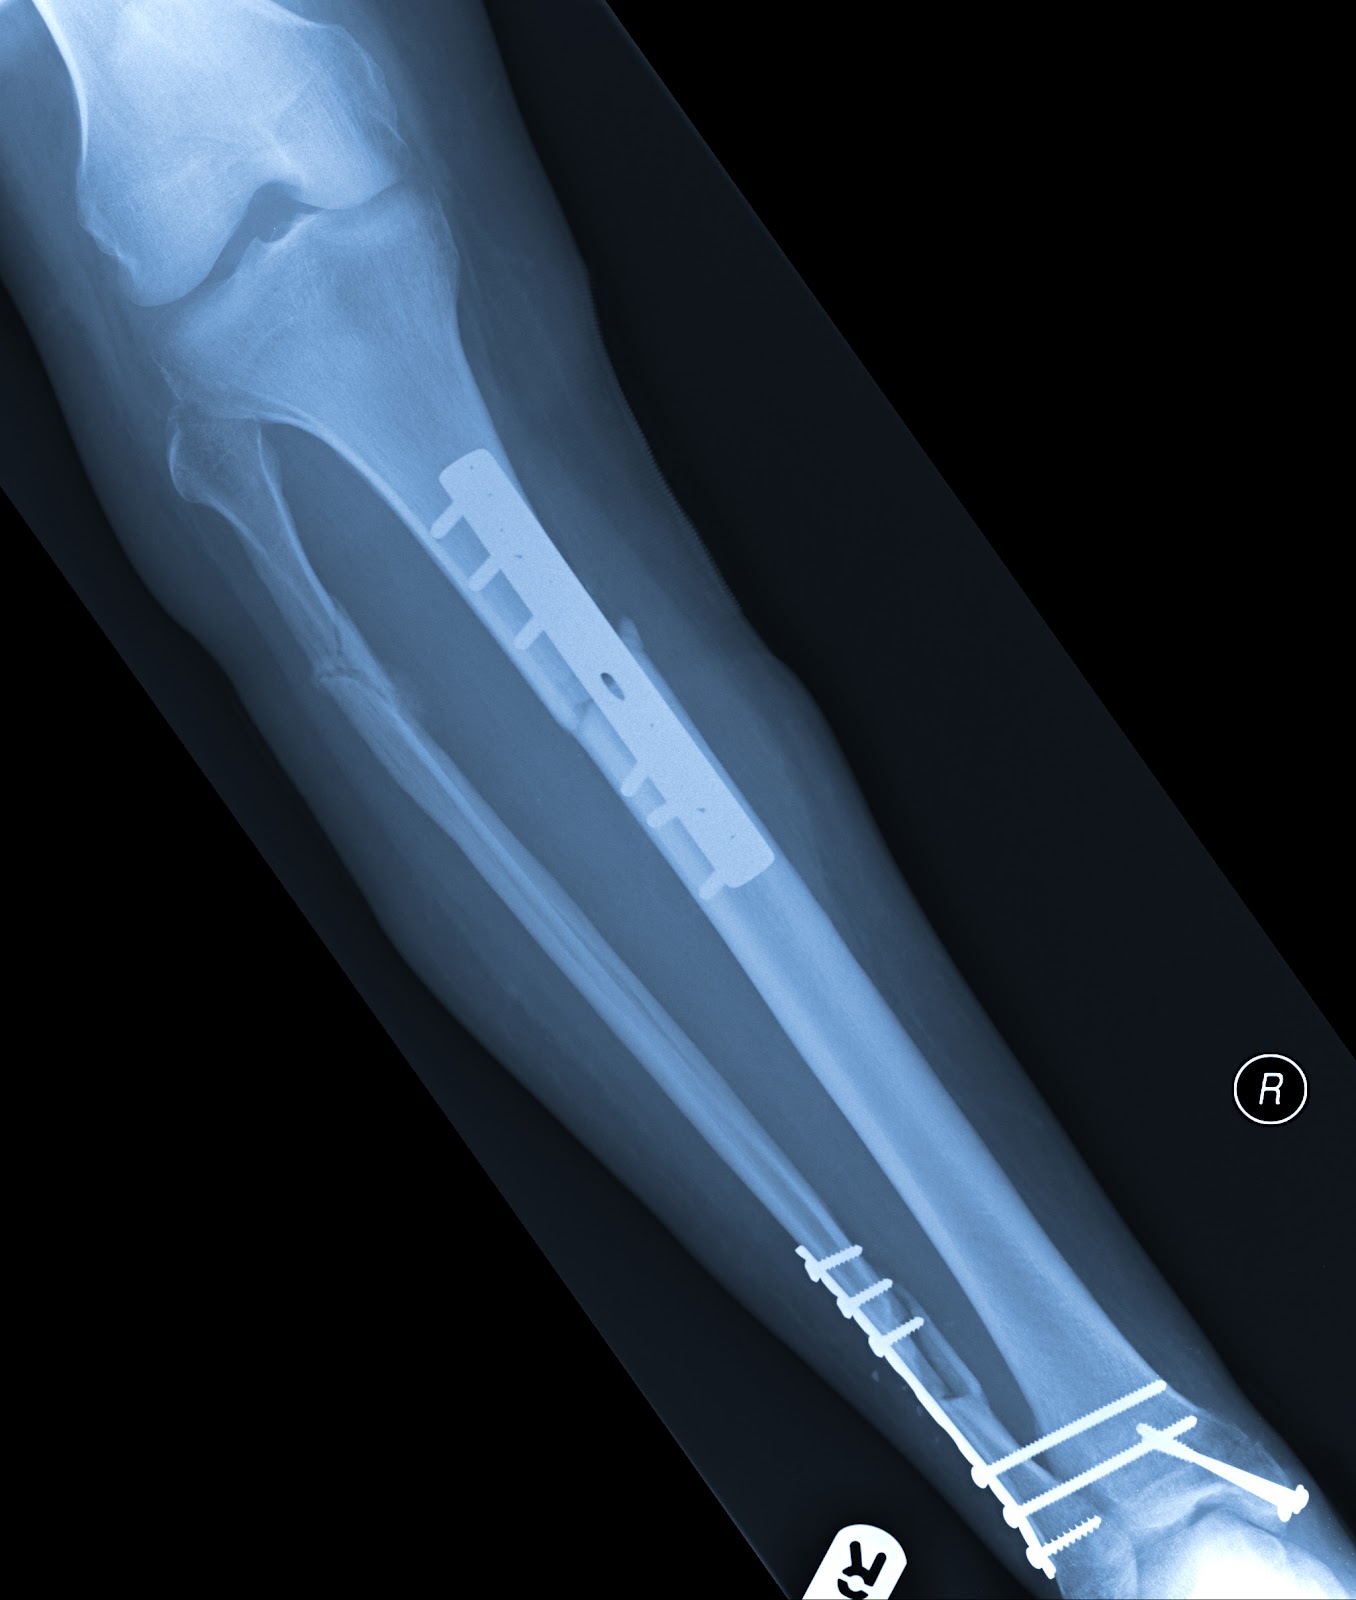

Whilst in this new room that was to be my home for many months, my injuries took a turn for the worst.